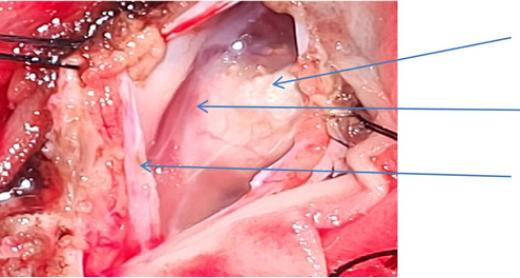

脊柱MRI显示硬膜内结节状病变(图2)在L2水平脊髓栓系的椎管后部,脊髓纵裂的特征(图3)和L4-5水平的背侧真皮窦,有脊髓栓系。CT扫描(图4)显示在L2、L3、L4、L5的后弓中的缺陷,以及在椎管、椎骨中的所有骶骨溶胶,在右侧L4/5小关节中注意到的部分融合,以及在椎管和L4/5水平的皮肤之间注意到的细的线性纤维化样束,可能是真皮窦。对颅脊髓轴进行筛查以排除脑积水和Arnold-Chiari畸形。根据临床和放射学表现,患者被安排手术。手术通过背部腰部区域的中线皮肤切口进行。暴露后,被证实为I型脊髓分裂畸形(SCM),硬膜外骨刺位于D12-L2椎骨水平。每个半索都有自己的硬膜囊和独立的脂肪脊髓脊膜膨出。使用高速钻在硬膜外显微镜下切除骨刺。硬脑膜以倒置的Y形方式打开。通过使用细致的显微神经外科解剖,对白线(脂肪瘤组织和脐带组织之间的界面)进行脂肪瘤组织的切除和脐带的解开。患者接受了脊髓松解术,同时切除了髓外硬膜内皮样肿块和脂肪瘤(图5和6)。术中模拟对肛周括约肌和下肢肌肉没有产生显著的反应。该患者接受了术中体感和运动诱发电位神经监测,未发现诱发电位间歇性降低。肿块的病理显示皮样囊性病变。

图5、术中图片显示附着于脂肪瘤病变的系留脊髓,术中使用神经监测棒进行神经监测

图、6术中图像显示硬脑膜、蛛网膜和下面的皮样肿块的开放视图